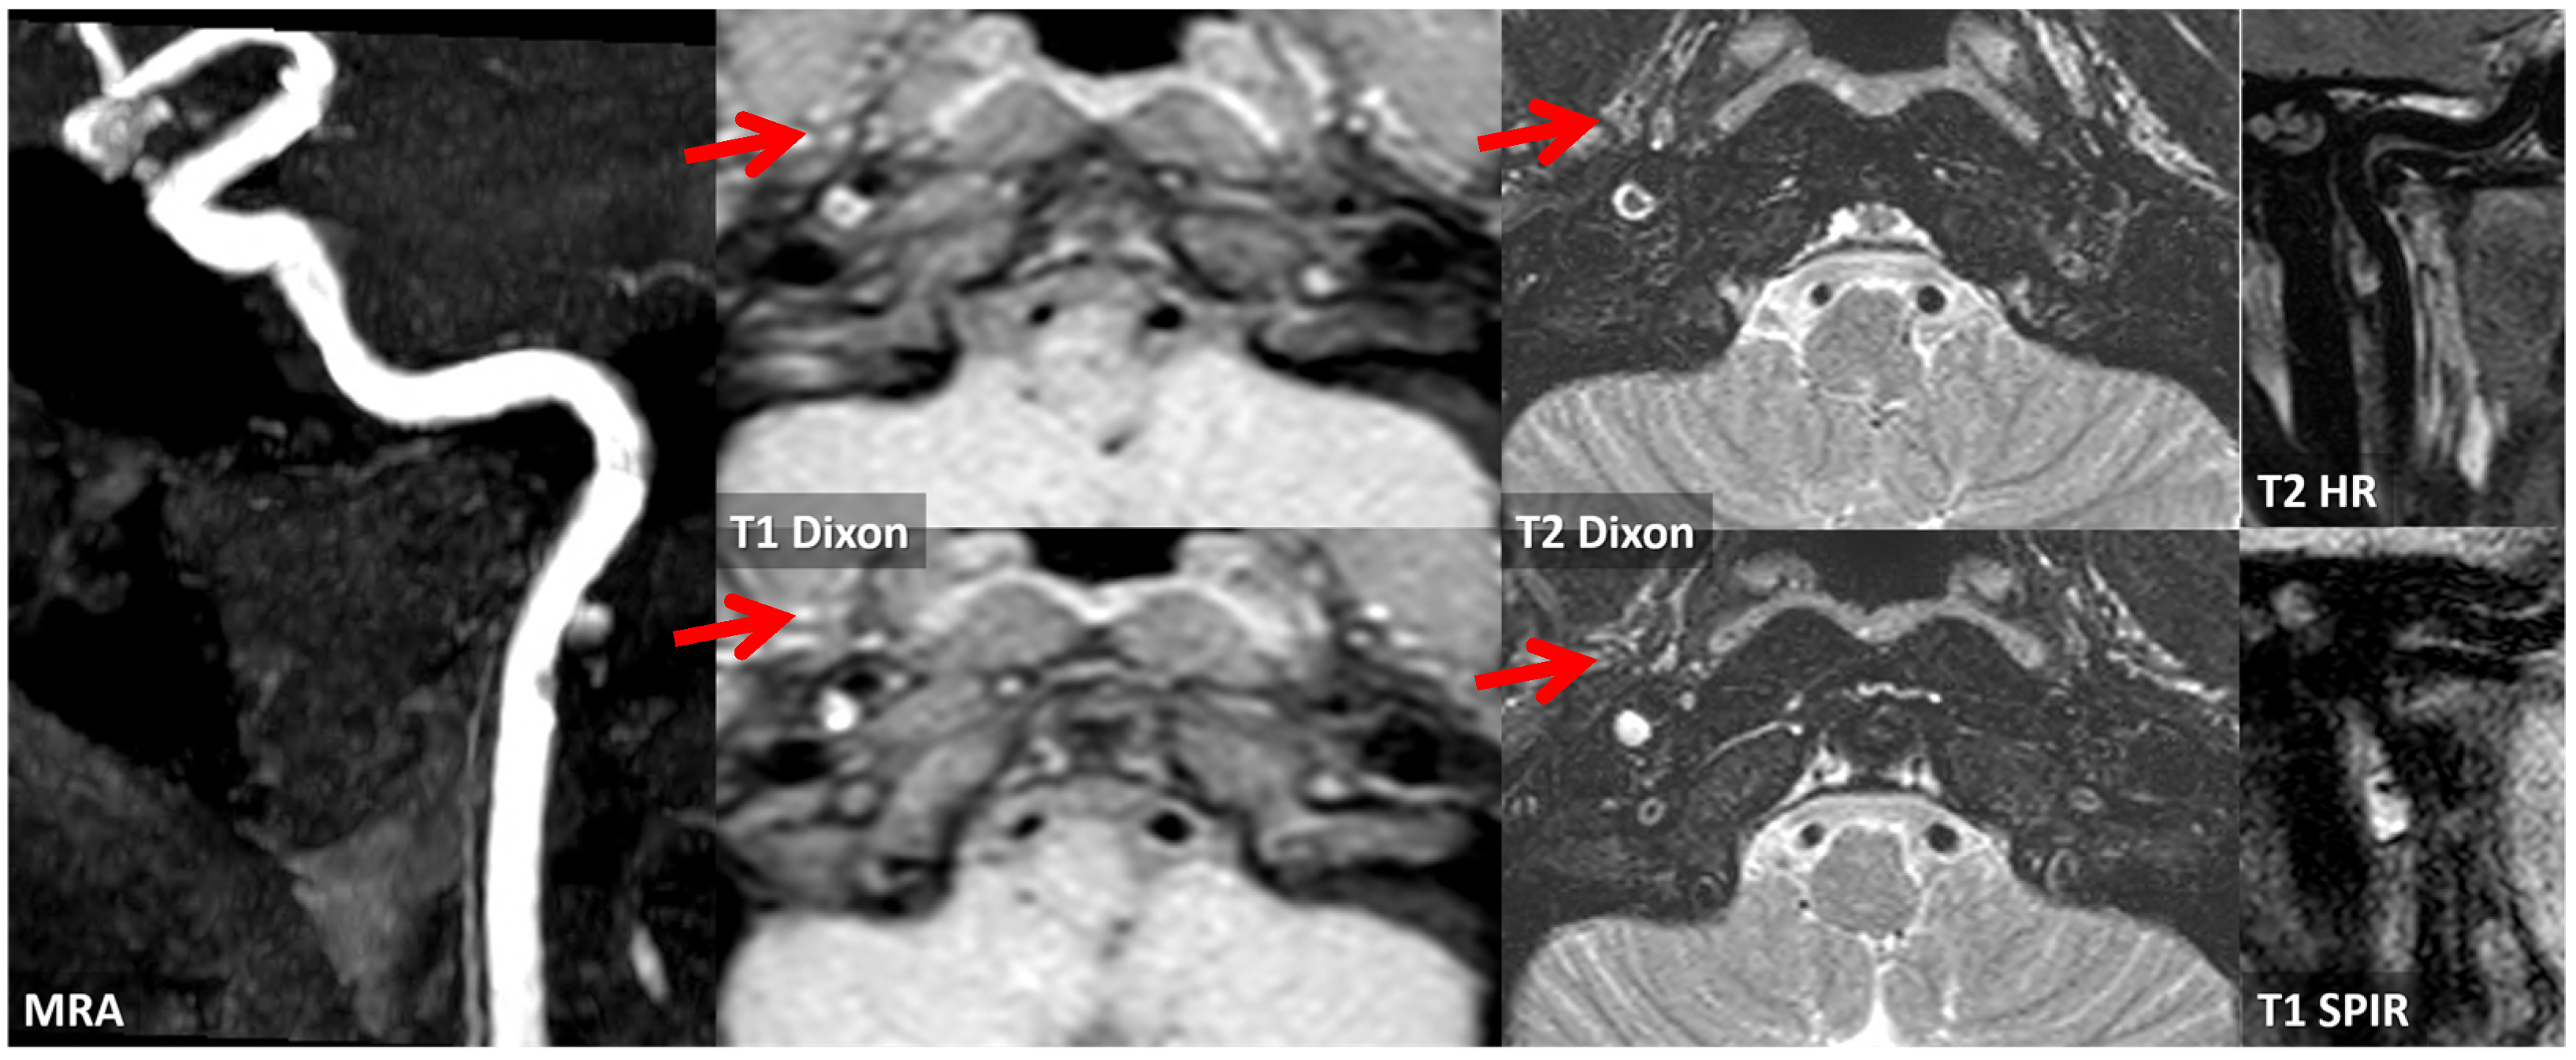

3.2. Case 2